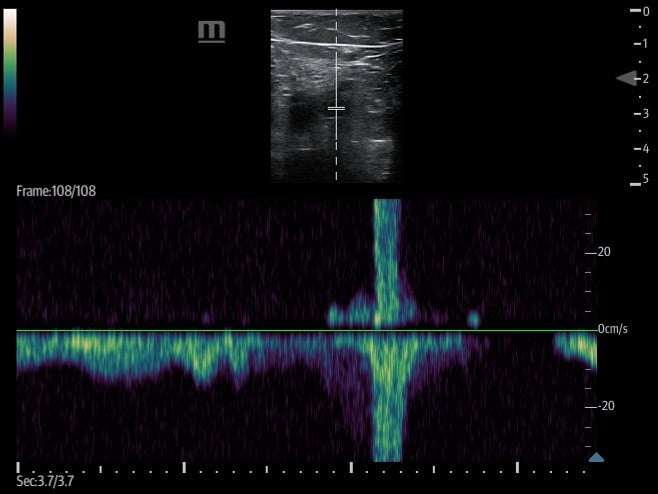

- Augmentation

- Involves placing the transducer proximally on the leg, typically at the CFV, and setting the ultrasound machine to color or pulsed wave Doppler mode.

- The calf is then squeezed or compressed along the venous system in order to increase venous return.

- Figure 16. Pulsed wave doppler demonstrating increased venous return with augmentation.

- If no DVT is present, there will be an increase in flow velocity noted on the ultrasound machine screen once the rush of blood passes the area where the transducer is placed.

- A lack of increased flow identified may be suggestive of an occlusive thrombus between the two points.

- Partial obstruction may can dampened flow when compared to the other side but can also cause subtle change in flow which can lead to false negative augmentation study.